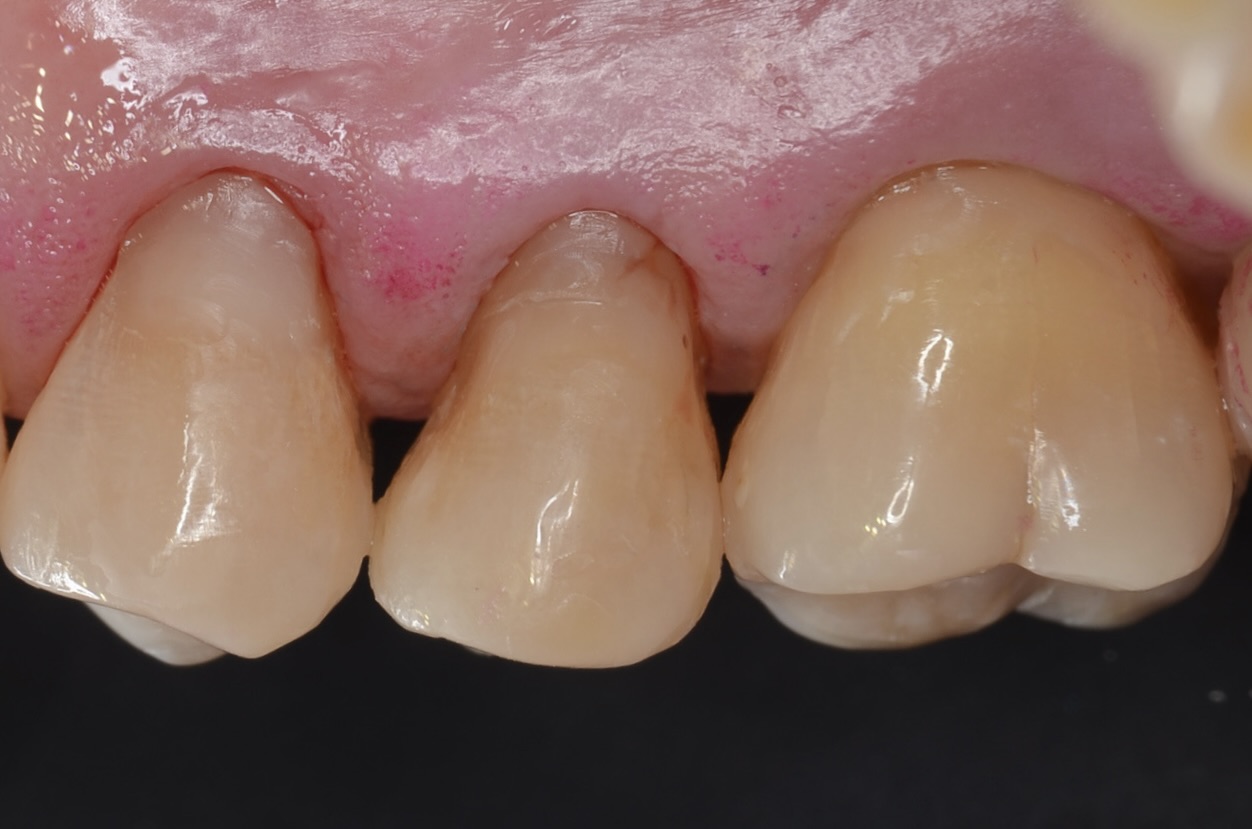

側方面観

歯頸部に古いレジンが充填されており虫歯になっています。 -

歯頸部の虫歯も打イレクトボンディングで治療しました。 -